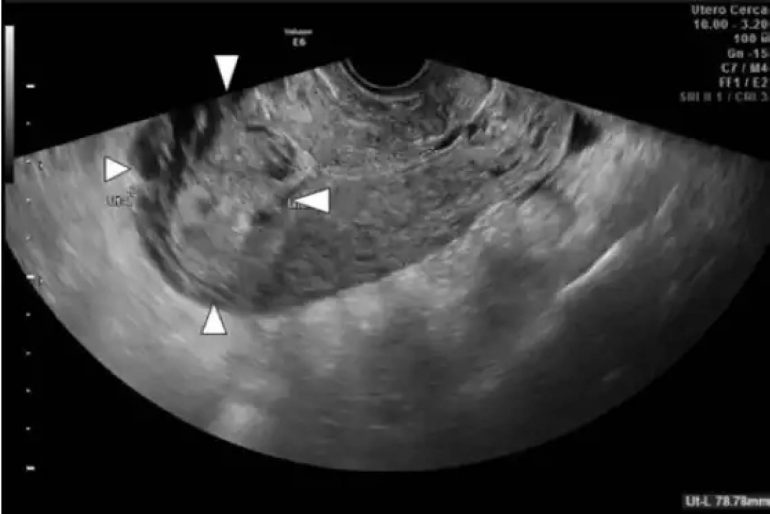

Restos Ovulares Pós-Legrado PuerperalA ocorrência de restos ovulares após um legrado puerperal é uma situação que também demanda atenção e cuidados médicos. O legrado puerperal é um procedimento cirúrgico realizado após o parto, com o objetivo de remover possíveis fragmentos de placenta ou tecido fetal que tenham ficado no útero.

Em alguns casos, mesmo após a realização do legrado puerperal, podem ocorrer restos ovulares que não foram completamente removidos. Esses restos podem causar sintomas como dor abdominal, sangramento excessivo e outros desconfortos. Por isso, é importante identificar e tratar esses restos ovulares para garantir a recuperação adequada da mulher após o parto.

A extração de restos ovulares pós-legrado puerperal é realizada da mesma forma que a extração de restos ovulares após um aborto espontâneo. O médico utiliza técnicas adequadas para identificar e remover todos os fragmentos que possam estar presentes no útero da paciente. É importante ressaltar que somente profissionais médicos qualificados devem realizar esse procedimento, garantindo assim a segurança e eficácia do tratamento.